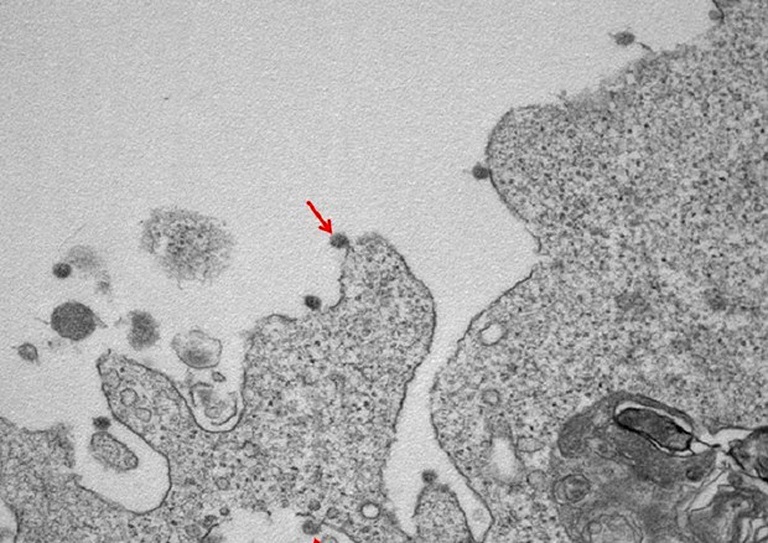

epa08339346 An undated handout picture made available by the Clinical Pathology Lab of the Department of Biomedical Sciences for Health (SCIBIS) at the University of Milan shows an arrow pointing to a novel coronavirus particle attached to cell membranes, displaying its typical glycoprotein spike 'corona' on the viral surface (issued 02 April 2020), seen in an electron microscope image, the first black and white portrait of the SARS-CoV2 virus, which causes the COVID-19 disease, isolated in the northern Italian region of Lombardy at the Sacco Hospital in Milan. EPA/UNIVERSITY OF MILAN/SCIBIS HANDOUT HANDOUT EDITORIAL USE ONLY/NO SALES

Imagini în premieră cu virusul care produce COVID-19! Imaginile sunt înfiorătoaret